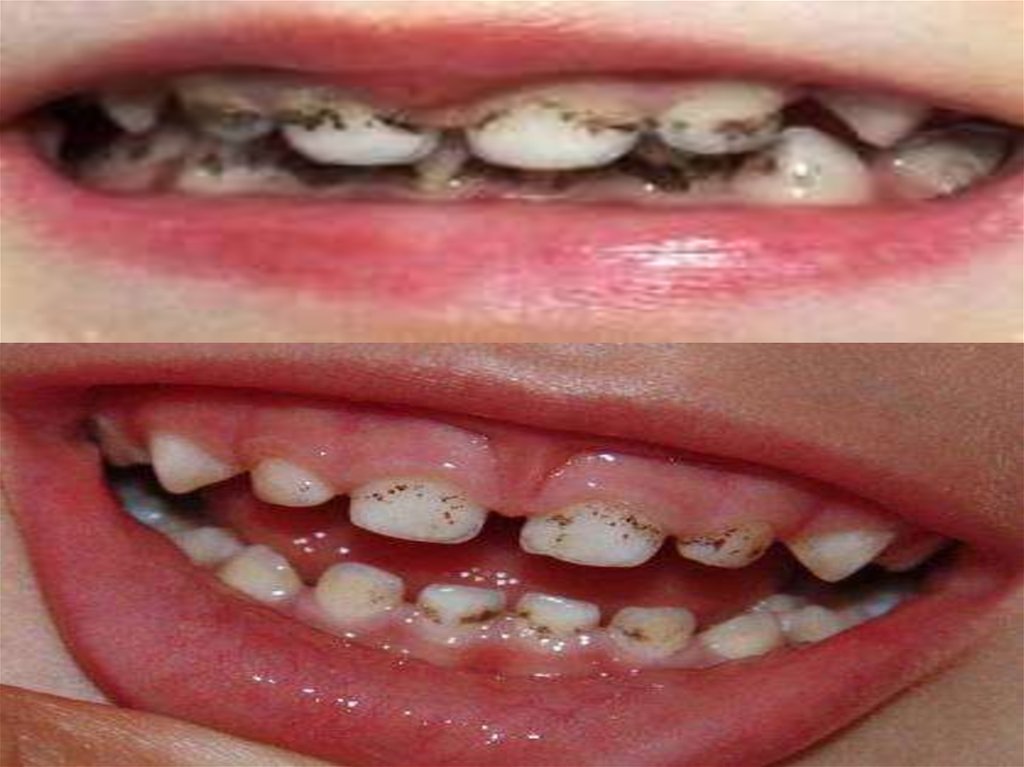

6.

7.

Тіс қағының түзілуі көп мөлшерде бір жағынан, ауыз

қуысының нашар гигиенасы немесе оның болмауы

кезінде байқалады. Басқа жағынан, мол қақ пен тіс

буылтығының түзілуі балада ауыз қуысында пайда

болатын табиғи өзін тазарту механизмдерінің

бұзылысымен байланысты:

гипосаливация немесе тұтқыр сілекей;

әртүрлі жазықтықтарда тістесу ауытқулары, тістердің

тығыз

орналасуы,

дұрыс

емес

жүргізілген

ортодонтиялық емдеу, сүт молярларды ерте жұлу

кезінде байқалатын жарақаттық окклюзия, бұл тұрақты

күрек тістердің жүктемесіне әкеледі;

ерін мен тіл үзбелерінің құрылысы мен бекінуінің

ауытқулары, ауыз қуысының ұсақ кіреберісі;